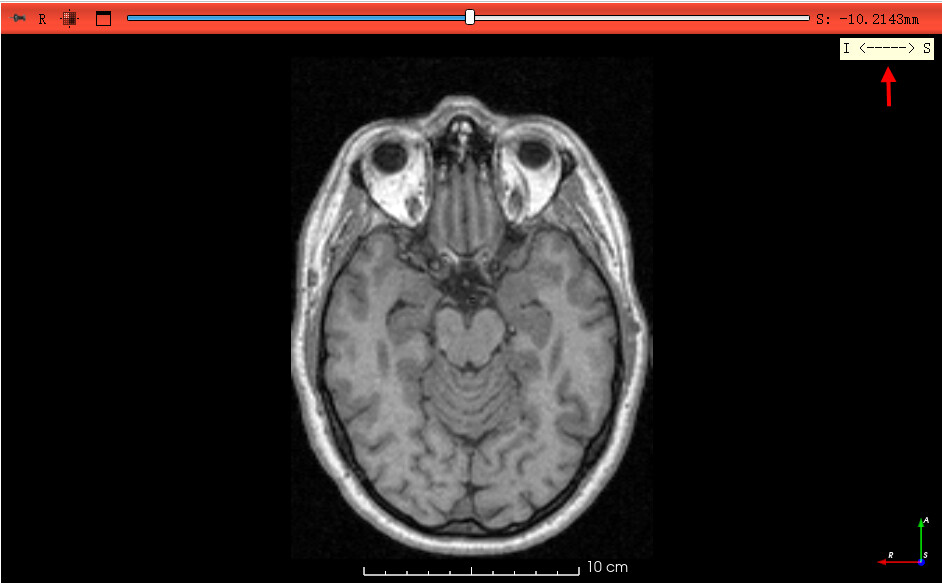

图像方向会立即翻转;确认正确后:

- 右键图像 → “Harden Transform”(应用变换)。

- 再保存为新的 NIfTI 文件。

- 翻转后可加载一个 DICOM 对照查看是否解剖一致。

- “Harden Transform” 后就永久修正了。

验证方法:加载 DICOM 原始数据与修正后 NIfTI 一起显示,确认解剖方向一致。

感谢老师的耐心、详细解答,已顺利将方向调整过来,另外,在将Nifti图像拖入新创建的Transform时,右边二维图像显示框会变黑,研究了一下,需要reset一下视野,图像就可正常显示!